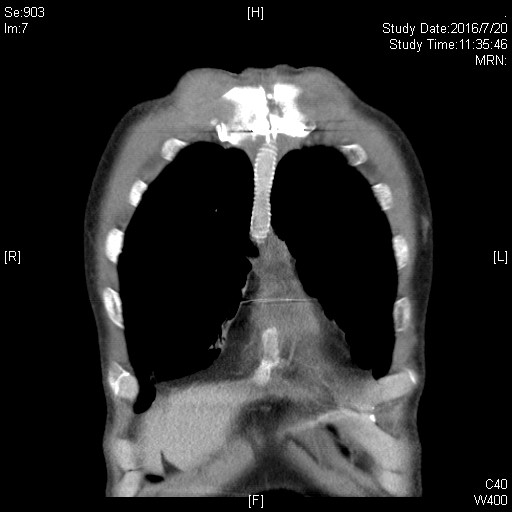

胸腺是前纵隔最主要的器官,最常见的原发肿瘤为胸腺瘤或胸腺瘤,以局部侵润性生长为主,出现症状时常已累及纵隔重要结构。治疗方式以手术切除为主,根治性切除能够显著延长生存,改善预后。患者胸腺肿瘤侵及上腔静脉、双侧无名静脉,临床表现为上腔静脉阻塞综合征。

手术采用胸骨正中切口,进胸后细致分离肿瘤与胸骨间粘连,充分探查后可见肿瘤侵及左右无名静脉、上中段上腔静脉、双侧纵隔胸膜、双肺上叶前缘、右膈神经,同时与头臂动脉前缘及左膈神经关系密切。经过充分游离周围粘连、切除双肺受累部分、清扫上纵隔淋巴结、剥离左侧膈神经,切断约3cm受肿瘤侵犯的右侧膈神经。陈东红主任判断肿瘤具备切除条件,需进行上腔静脉重建。手术采用Gore-Tex带环人工血管行上腔静脉置换顺势吻合,以CV-6缝线连续缝合。先以人工血管建立左无名静脉-右心耳血管桥,完整切除肿瘤后搭右无名静脉-上腔静脉血管桥。检查吻合口无渗血,血管桥无扭转。而后由骨科潘勇卫主任进行了右膈神经的对端吻合。手术彻底肿瘤切除,人工血管充盈,心脏搏动有力。肺部切缘采取手工缝合,术后肺膨胀良好无漏气。切除肿瘤标本直径约10cm,手术时间约8小时。术后返回监护病房,3天内拔除所有引流管。